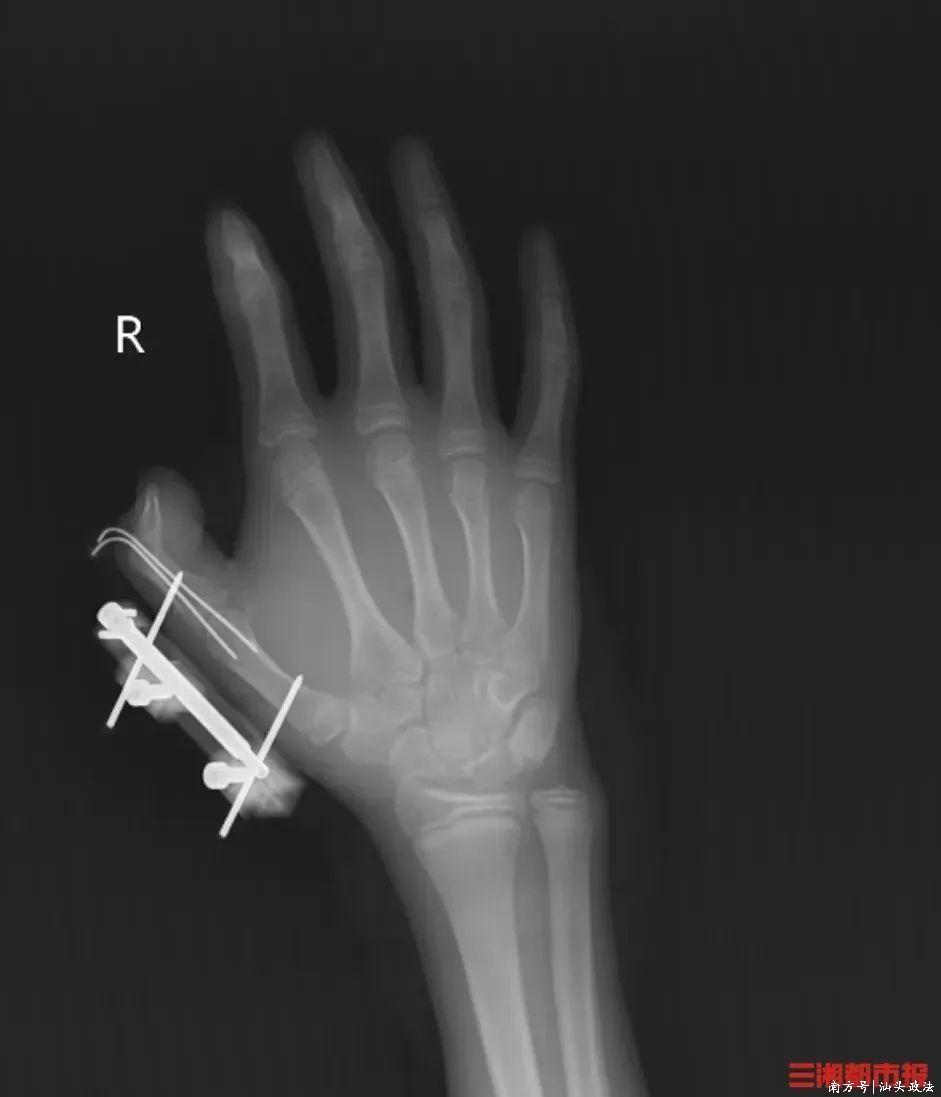

倏地,密封袋里的干冰发生爆炸,维维的右手倏地鲜血直流,拇指虎口处被撕开一起约10厘米的伤口,深可见骨,肌肉组织断裂外露,还伴跟着拇指骨折、要道脱位,统共拇指完全失去知觉。

见状,家东说念主马上带他到当地病院包扎,随后蹙迫转往湖南省东说念主民病院兄弟显微外科。经调理,维维的拇指保住了,但后续还需始终康复考试,智力逐渐规复手部精细算作功能。